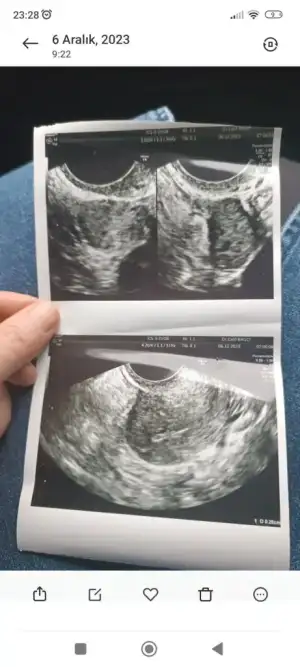

Çok ta anlaşılmıyor ya da düz bir açıdan çekilmiş bak benim eskilerden birini atıyorum şimdi ama resimden ziyada sağ alt köşesinde kaç ml olduğu yazıyor 1,87 2,44 cm yazıyor mesela senin kağıdın bir tarafında yok mu bu bilgi

Sizin en altta küçük bir tane yazıyor ama çok küçük diye mi acaba doktor yok dedi, o da olabilir. Evet progesteron testiyle anlaşılıyor o ay yumurtlama olup olmadığı, onu da ortalama döngü 28 gün üzerinden hesapla 21. gün istiyorlar, içinde kalcağına bence baktır canım aklında kuşku olmasın en azından

Ultrason fotoğrafımda işaretlenmiş iki nokta gördüm onların folikül olduğunu tahmin ediyorum ama dediğim gibi çok kötü bir doktora denk geldim kafam karıştı. Önerdiğiniz hormon testini vereceğim çok teşekkür ederim 💞🌺

O karartılar zaten kist değilse ki olsa illa söylerdi , aynen folikül oluyor ama çok küçük diye herhalde yok deyip geçiştirdi mi ne yaptıysa. Kadın doğum doktorunda doktor işi şans işi gerçekten inanıyorum ben artık.geçen gün öyle birine denk geldim ne sorsam tüp bebekçiler söylesin dedi adam sonra çıktım şikayet ettim adamı o kadar sinir oldum , sen ne işe yarıyorsun o zaman diyecektim ama eşim yanımda laf olur kavga olur bilmem ne derken bide sağlıkta şiddet haberlerinden biri de biz olmayalım diye tuttum kendimi velhasıl. Ama şikayetimi de ettim , ulaşır ulaşmaz bilmem ama sinirimi kustum o da yetti bana😂